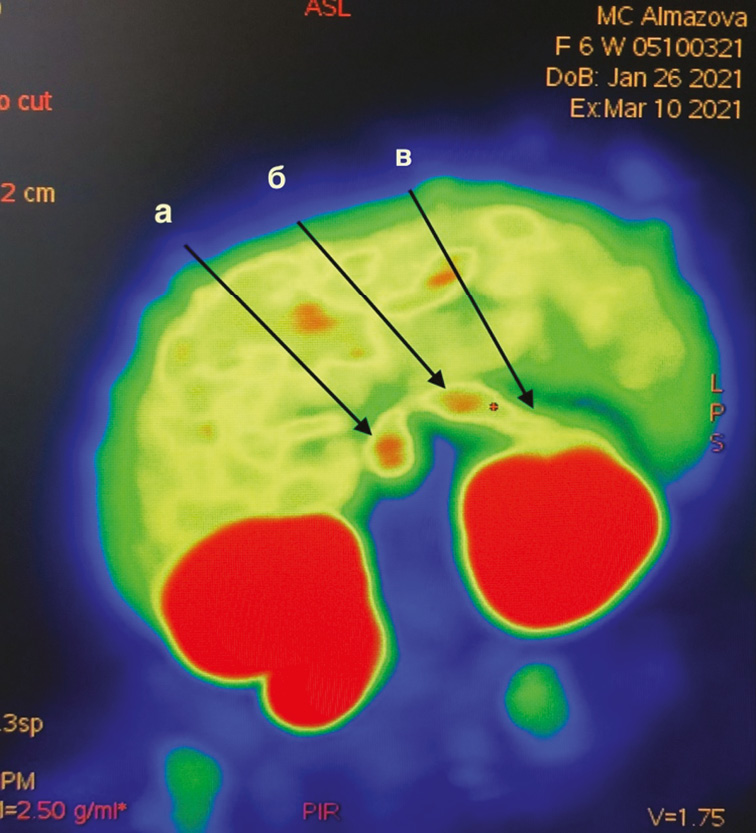

11.03.2021 в возрасте 1,5 мес. проведена ПЭТ/КТ в Центре позитронно-эмиссионной томографии ФГБУ «НМИЦ им. В.А. Алмазова»; РФП: 18F-ДОФА, активность 18 мБк; лучевая нагрузка: расчетная 2,1 мЗв. Описание: на серии ПЭТ-томограмм органов брюшной полости и забрюшинного пространства отмечается диффузно-неоднородная гиперфиксация 18F-ДОФА в паренхиме железы с наибольшей аккумуляцией РФП в теле и головке поджелудочной железы (панкреатический индекс головка/тело на 10-минутном скане, выполненном через 50 мин после инъекции РФП, 1,05, головка/хвост — 1,2) (рис. 1).

Рис. 1. Картина диффузного поражения поджелудочной железы по данным позитронно-эмиссионной томографии, совмещенной с компьютерной томографией: а — головка, b — тело, с — хвост

Fig. 1. View of diffuse lesions of the pancreas according to PET/CT: a — head; b — body; c — tail

Очаги патологического накопления 18F-ДОФА в других органах и тканях, представленных в зоне сканирования, не обнаружены. Физиологическое накопление РФП в паренхиме печени, паренхиме и чашечно-лоханочных системах почек, мочеточниках, зонах роста костей. Заключение: ПЭТ-картина соответствует диффузной форме врожденного гиперинсулинизма.

В возрасте 1,5 мес. 15.03.2021 переведена на пост интенсивной терапии отделения детской хирургии пороков развития, где подготовлена к операции. Перед операцией результаты проведенной ПЭТ/КТ обсуждены совместно врачом-радиологом и бригадой оперирующих хирургов, при этом было обращено внимание на то, что, несмотря на низкие панкреатические индексы, визуально складывается впечатление о более низком распределении РФП в области хвоста по сравнению с головкой и телом (рис. 1).